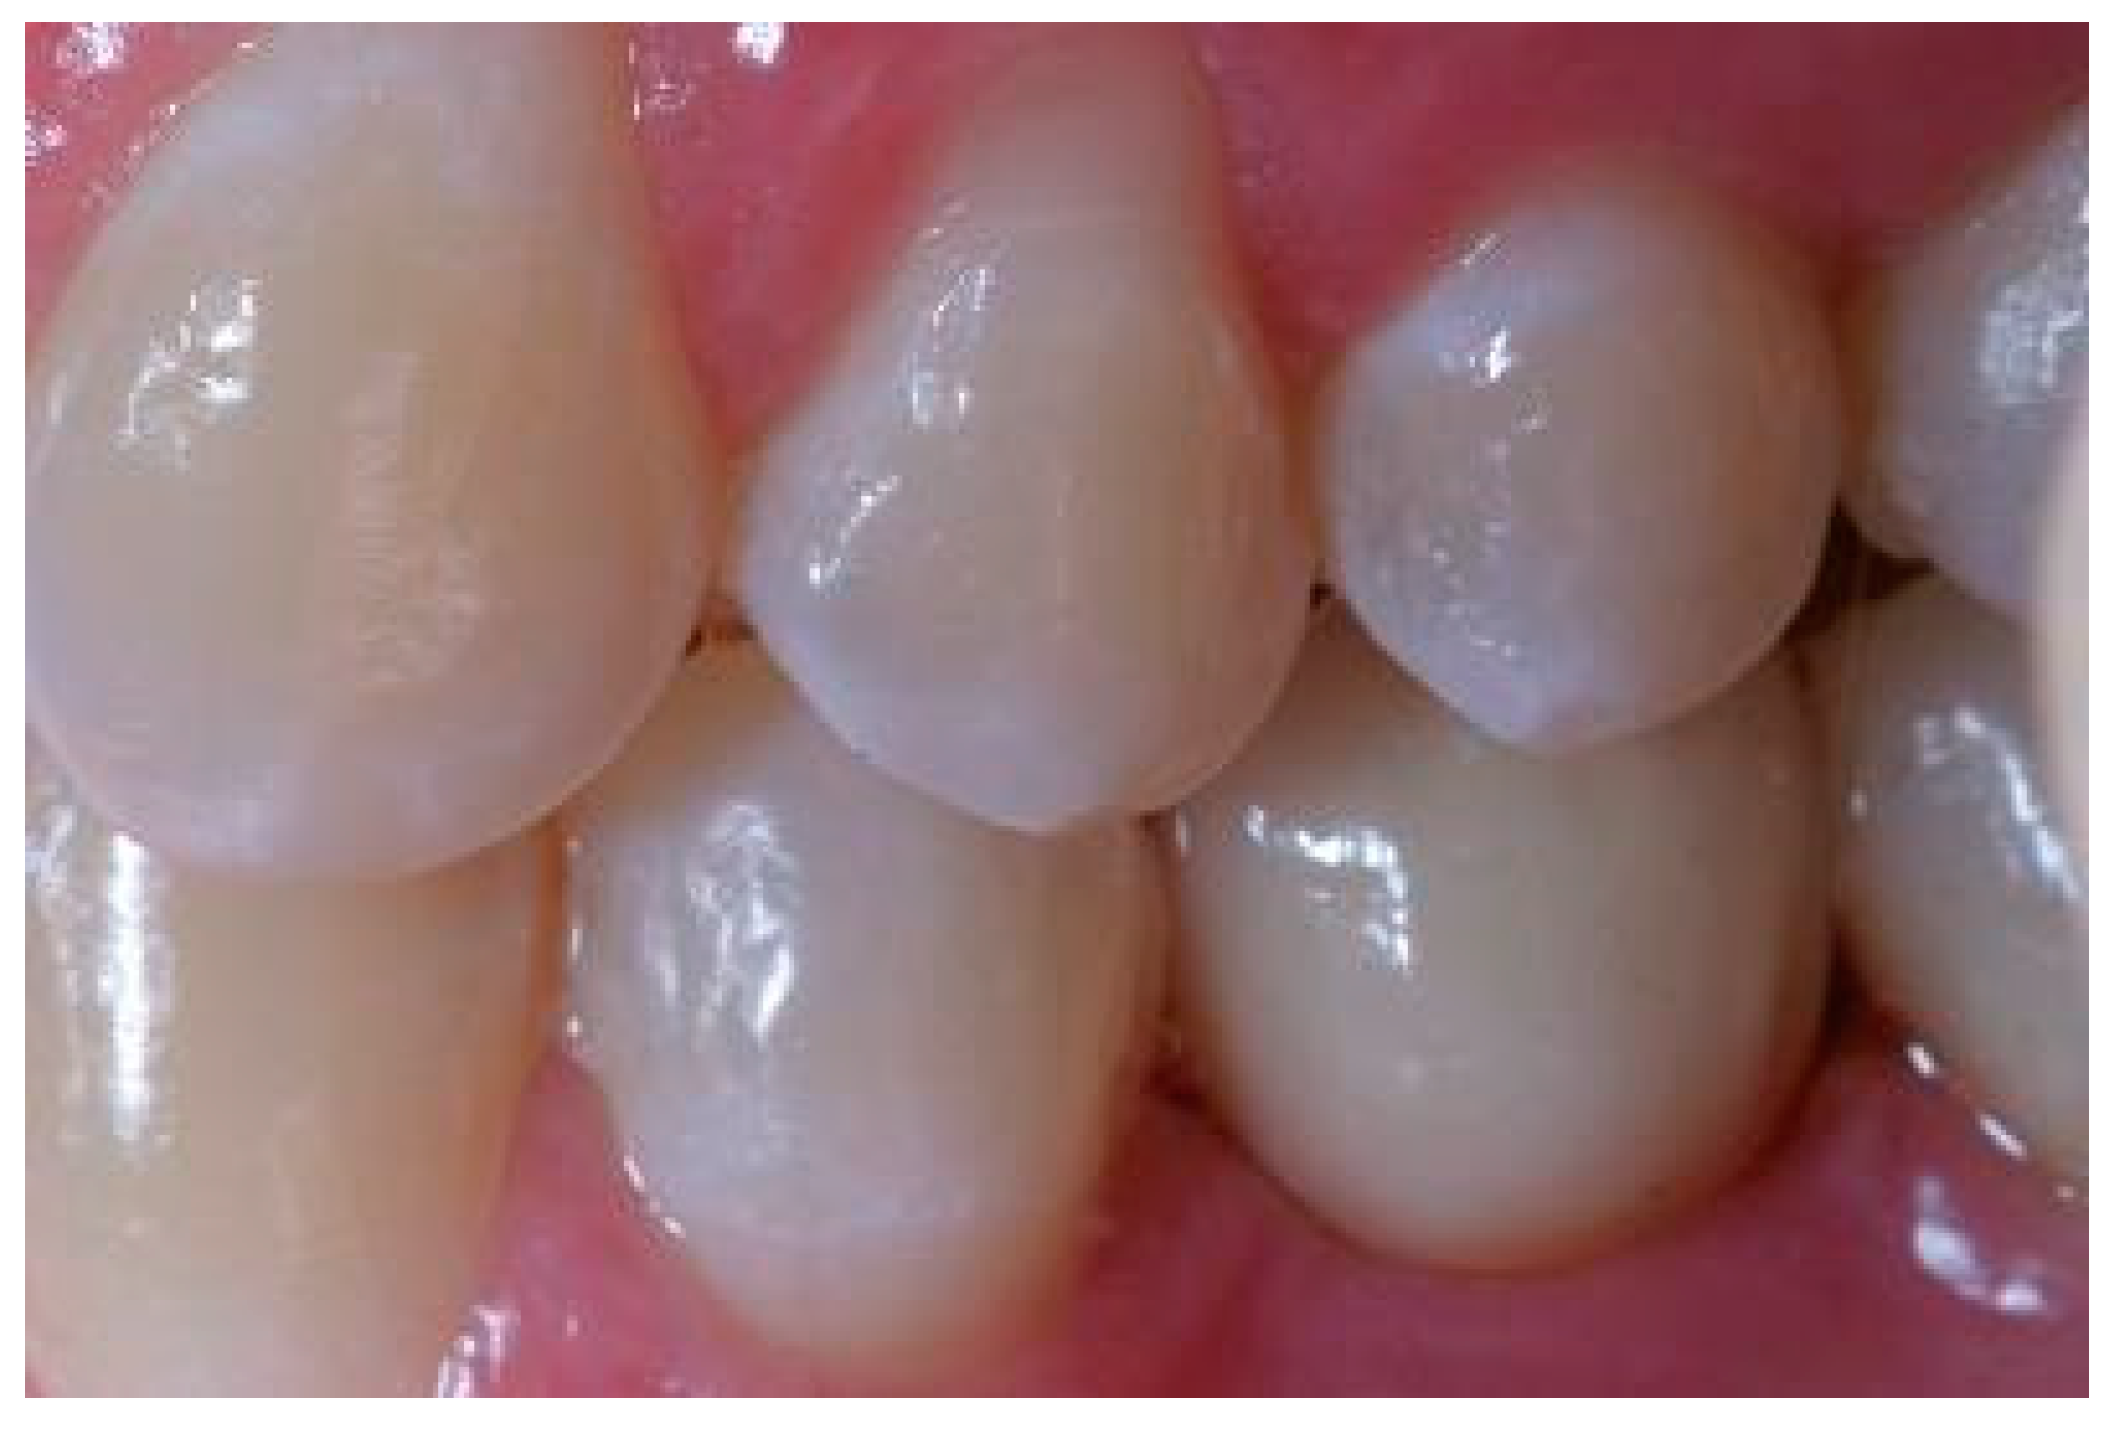

Appendix A. Exemplary Photographs and Radiographs from a Patient at Different Examination Time Points and a Positive Outcome

Appendix B. Exemplary Photographs and Radiographs from a Patient at Different Examination Time Points and a More Negative Outcome